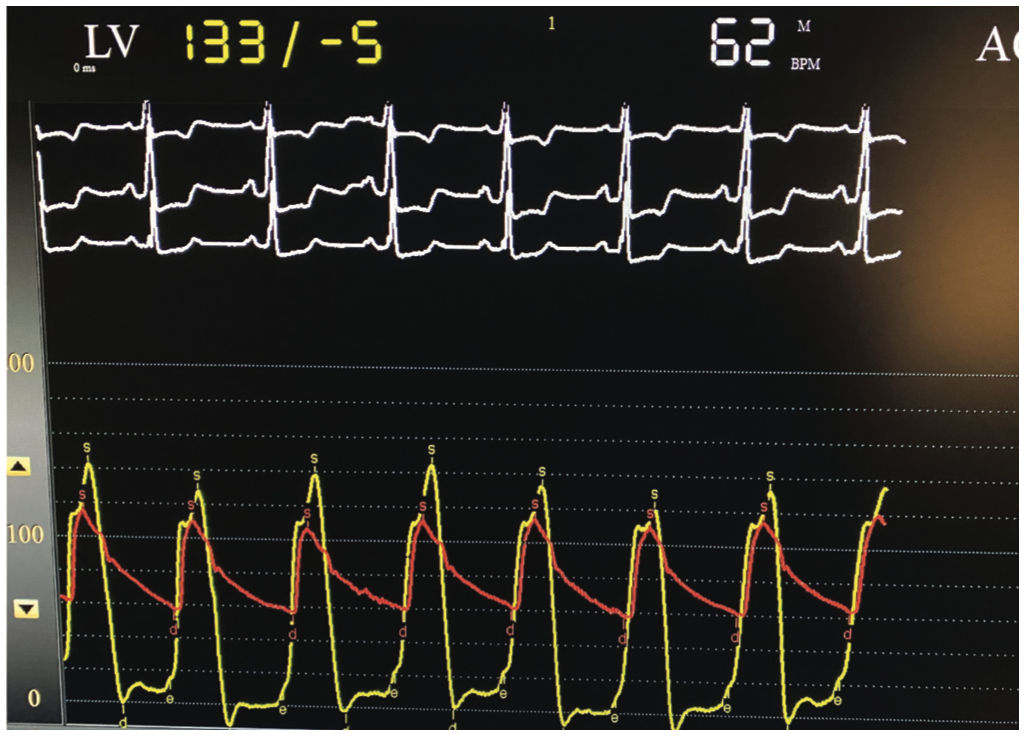

Femoral access was gained with a 6.0 Fr, 24 cm Arrow-Flex sheath (Telflex) (note longer sheaths can be used if desired). After routine coronary angiography, the aortic valve was crossed with a 5 Fr Judkin right 4.0 (JR4) catheter over a standard .014-inch J wire. Alternatively, to save a step, Amplatz left guiding catheters and moveable or fixed core straight wires can be directly placed in the LV. Simultaneous LV and aortic pressures were measured using the femoral long sheath pressure as a surrogate for the ascending aortic pressure, after verifying that aortic root and long sheath pressures were identical and superimposable, which is another technique useful for quickly measuring LV-aortic gradients. The use of this gradient as a surrogate for aortic root-to-LV gradients has been controversial; however, we find it to be suitable for most routine clinical decision making. Subsequently, the 5 Fr JR4 catheter was exchanged for a 6 Fr JR4 guide catheter over a standard .035-inch exchange-length J wire and the aortic valve was crossed with a JR4 guide catheter. An .014-inch Runthrough coronary wire (Terumo) was advanced into the LV. The guide catheter was pulled back into the ascending aorta, leaving the Runthrough in the LV. Next, a Twin-Pass microcatheter was advanced into the LV over the Runthrough wire. Simultaneous LV and aortic pressures were measured using the Twin-Pass and guide catheter. During pullback, premature ventricular contractions (PVCs) were induced when necessary with the Runthrough wire, and resting and provoked gradients were measured precisely, easily, and repetitively at various locations within the LV using LV-aortic pullbacks of the Twin-Pass over the guidewire. The pressure gradient, when measured by using the femoral sheath as a surrogate for the ascending aortic pressure and by directly measuring the ascending aortic pressure with the JR4 catheter, correlated well between the two techniques. The absence of a transvalvular pressure gradient and the presence of a LV outflow gradient with Brockenbrough-Braunwald-Morrow sign were evident, and these dynamic obstructive hemodynamics were easily measured and demonstrated with guidewire-provoked PVCs. Once measurements were complete, all catheters and wires were removed. Hemostasis was achieved with the use of an Angio-Seal (Terumo). Figures 1-5 show the instruments that were used and the waveforms that were obtained in this case.

The use of the Twin-Pass catheter within a standard guiding catheter is helpful for the simultaneous measurements of aortic and LV pressures and LV outlow tract gradient measurements. In our experience, this technique also correlates well with the use of the femoral arterial sheath as a surrogate for the ascending aortic pressure. In the era of the Langston catheter recall, this technique may be used for the measurement of aortic stenosis and left ventricular outflow tract obstruction. An .014-inch Runthrough wire can induce PVCs to elicit the Brockenbrough-Braunwald-Morrow sign and further differentiate valvular aortic stenosis from hypertrophic obstructive cardiomyopathy.